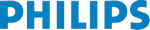

Affiniti 70 — это инновационная ультразвуковая система, которая отвечает потребностям отделений ультразвуковой диагностики, работающих с большой нагрузкой, и позволяет своевременно получать надежные результаты. Созданный на основе проверенных технологий Philips, этот эффективный и надежный аппарат способен быстро получить диагностически ценные изображения даже для наиболее сложных пациентов. Продуманный дизайн и исключительная простота использования помогут обеспечить эффективную диагностику в ежедневной практике.

Система Affiniti 70 оснащена датчиками PureWave, которые позволяют увеличить глубину проникновения при сканировании сложных пациентов. В результате, один и тот же датчик можно использовать для диагностики пациентов различного телосложения. Благодаря точному формированию луча система помогает обеспечить превосходное пространственное и контрастное разрешения, высокую однородность отображения тканей, а также низкие уровни артефактов и шума на изображении.

- Абдоминальные исследования

- Сосудистые исследования

- Максимальная глубина визуализации: 30 см

- Режимы визуализации: В, М, CWD, PWD, анатомический М-режим, цветной М-режим, энергетический и цветной допплеры, режимы 3D/4D